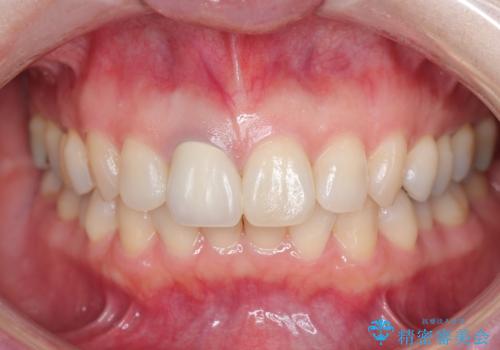

問題なく綺麗な被せ物が入りました。

保険の被せ物は安価ですが劣化しやすいため着色しやすい素材です。

セラミックの素材は劣化することなくまた虫歯の再発のリスクも下げてくれます。